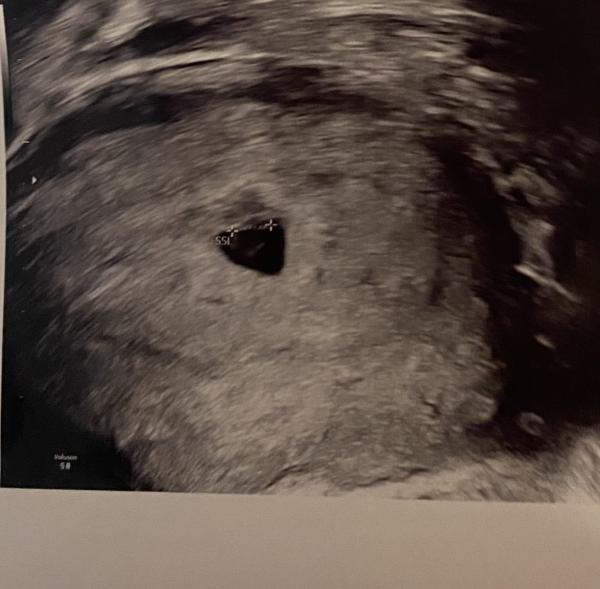

Hallo  ich bin jetzt bei 13+2 Habe hier ein Bild von 7+4 mich interessiert was die ramzi Methode sagt. Mein bauchgefühl ist Mädchen. Wenn wer es erkennt gerne schreiben ☺️ Ist aktuell die 3 Schwangerschaft  Bild 1 ist aktuelle (7+4) Bild 2 ist 2 Schwangerschaft ist ein Mädchen (6+1) Bild 3 ist 3 Schwangerschaft ist ein Junge (6+4)